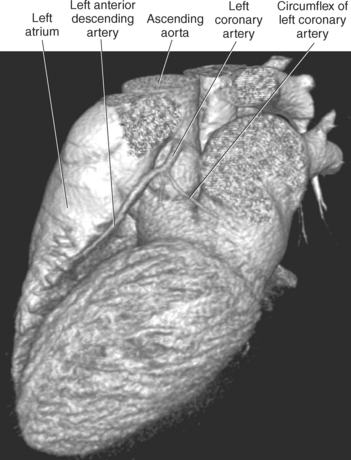

The two main coronary arteries are the first vessels to branch off the ascending aorta (Figures 6.91 and 6.92). The right coronary artery arises from the base or root of the aorta (right aortic sinus) and passes anteriorly between the pulmonary trunk and right atrium to descend in the coronary (atrioventricular) groove. As it reaches the diaphragmatic surface, it gives off a right marginal branch that runs toward the apex of the heart. The right coronary artery then turns to the left and enters the posterior interventricular groove, where it gives off the posterior interventricular branch (posterior descending artery). The posterior interventricular branch continues to descend along the interventricular groove toward the apex, where it anastomoses with the left anterior descending artery of the left coronary artery. The right coronary artery and its branches supply the right atrium, right ventricle, interventricular septum, and the sinoatrial (SA) and atrioventricular (AV) nodes. It also supplies a portion of the left atrium and ventricle (Figures 6.92 through 6.96). The left coronary artery arises from the left aortic sinus and passes to the left between the pulmonary trunk and left atrium to reach the coronary groove (Figures 6.91 and 6.92). Soon after reaching the coronary groove, the left coronary artery divides into the circumflex and left anterior descending (interventricular) arteries. The circumflex artery winds around the left border of the heart to the posterior surface, where it gives off the left marginal artery. The left anterior descending artery (LAD) descends in the anterior interventricular groove toward the apex of the heart, where it reaches the diaphragmatic surface to anastomose with the posterior descending artery. The left coronary artery and its branches supply the interventricular septum, including the AV bundles, and most of the left ventricle and atrium (Figures 6.97 through 6.99).